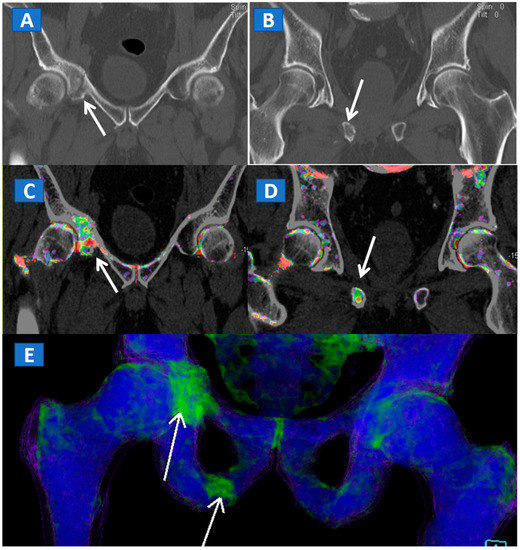

Figure 3.

A 51-year-old male with a non-displaced left cervical fracture. On the coronal standard radiograph (A), a meshed fracture is suspected on the left side because of an apparent cortical irregularity (arrow). On the corresponding standard reconstructed 1 mm CT image (B), a subtle cortical irregularity is confirmed (arrow). On the corresponding DECT reconstructed coronal 1 mm image (C), severe BME clearly delineates the fracture line (arrow), which is surrounded by a mild oedema halo involving the trochanteric region.

Figure 4.

A 61-year-old female with non-displaced fractures of the right iliac and pubic bones. On the standard coronal 1 mm CT images (A,B) the iliac fracture is well depicted (arrow in (A)), whereas the pubic fractures could be easily missed (arrow in (B)). The presence of BME on the corresponding 1 mm coronal reconstructed DECT images (C,D) confirms the non-displaced fractures. The 3D coronal DECT map (E) yields a clear picture, depicting the fractures of the right side and ruling out the presence of BME on the left side.